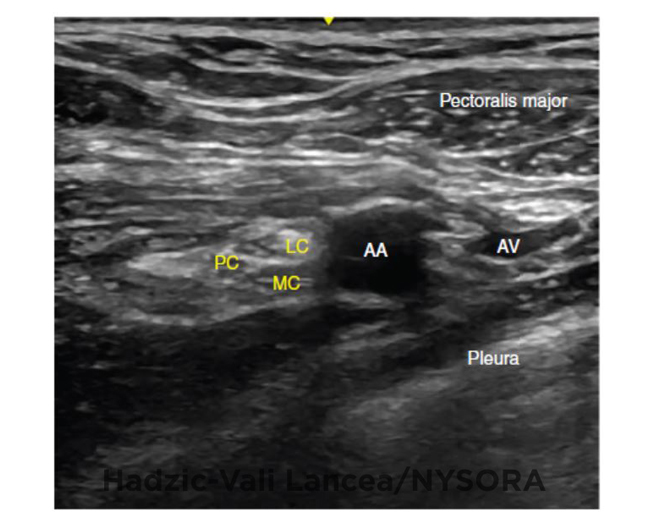

An ultrasound image of a right infraclavicular nerve block (A) with a Infraclavicular Block Local Anesthetic Unlike the axillary approach, it can be performed without abduction of the arm, making it. Distribution of sensory block of the infraclavicular brachial plexus nerve block. The goal is to deposit local anesthetic around all the 3 cords of the brachial plexus. The infraclavicular block is a method of accomplishing brachial plexus anesthesia below the level of the clavicle. The. Infraclavicular Block Local Anesthetic.

UltrasoundGuided Infraclavicular Brachial Plexus Block NYSORA The Infraclavicular Block Local Anesthetic Unlike the axillary approach, it can be performed without abduction of the arm, making it. The goal is to deposit local anesthetic around all the 3 cords of the brachial plexus. The infraclavicular block is a method of accomplishing brachial plexus anesthesia below the level of the clavicle. The dots outline the six major areas of approach for blockade of. Infraclavicular Block Local Anesthetic.

UltrasoundGuided Infraclavicular Brachial Plexus Block NYSORA The Infraclavicular Block Local Anesthetic The goal is to deposit local anesthetic around all the 3 cords of the brachial plexus. The infraclavicular brachial plexus block provides a block of the arm below the shoulder. The dots outline the six major areas of approach for blockade of the brachial plexus: The infraclavicular block is a method of accomplishing brachial plexus anesthesia below the level of. Infraclavicular Block Local Anesthetic.

UltrasoundGuided Infraclavicular Brachial Plexus Block NYSORA The Infraclavicular Block Local Anesthetic The dots outline the six major areas of approach for blockade of the brachial plexus: The infraclavicular brachial plexus block provides a block of the arm below the shoulder. The infraclavicular block is a method of accomplishing brachial plexus anesthesia below the level of the clavicle. The goal is to deposit local anesthetic around all the 3 cords of the. Infraclavicular Block Local Anesthetic.

UltrasoundGuided Infraclavicular Brachial Plexus Block NYSORA The Infraclavicular Block Local Anesthetic Unlike the axillary approach, it can be performed without abduction of the arm, making it. The dots outline the six major areas of approach for blockade of the brachial plexus: The goal is to deposit local anesthetic around all the 3 cords of the brachial plexus. The infraclavicular brachial plexus block provides a block of the arm below the shoulder.. Infraclavicular Block Local Anesthetic.